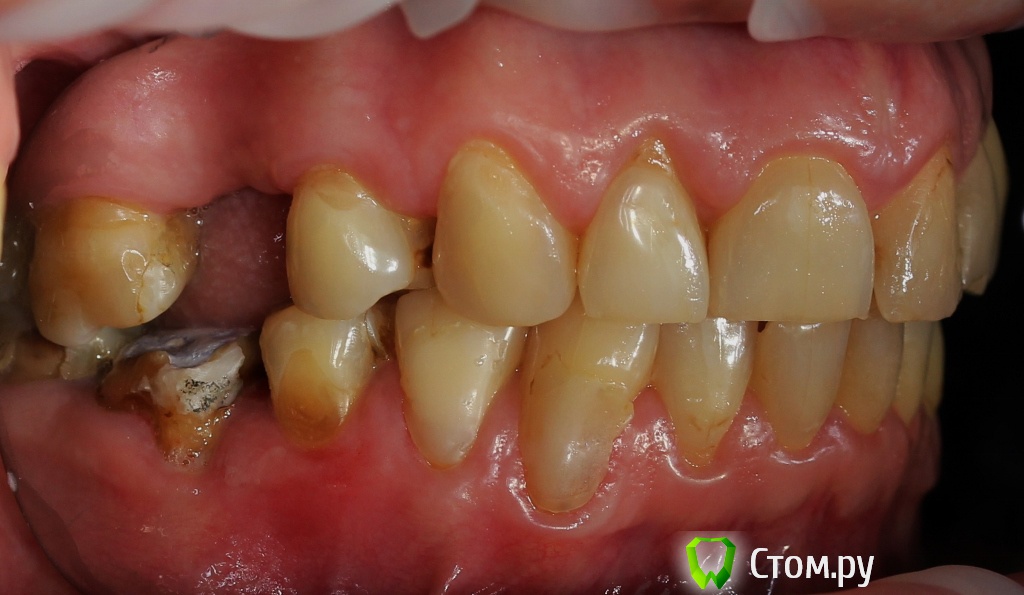

Dr.Sham Опубликовано 21 октября, 2014 Поделиться Опубликовано 21 октября, 2014 (изменено) Пациентка 55 лет с онкологией в прошлом.Аутоиммунный тиреоидит.Хочет красивые зубы, которыми можно жевать.Суставной компонент я не диагностирую, щелчков и посторонних шумов при открывании рта нет. Мышцы без гипертонуса, пальпаторно боли отмечает со стороны крыловидной медиальной и латеральной мышц слева.Фотки. Рентген. КТ пока не делал, хочется сделать с шаблоном, но пока с планом лечения не определились.Брекеты не хочет, каппы хочет, но я не знаю возможности лечения на каппах и доктора ответственного (С-Пб.) Фото: Модели в артикуляторе: ОПТГ Изменено 21 октября, 2014 пользователем Dr.Sham Ссылка на комментарий